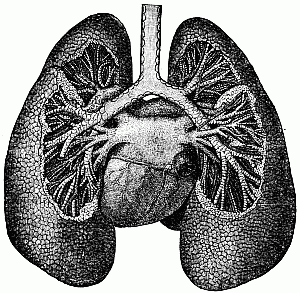

| XV. | —The Lungs | 97 |

In the chest, are the heart and the lungs.

These neighbors are the lungs. They are[98] in the chest on each side of the heart. When you breathe, their little air-cells swell out, or expand, to take in the air. Then they contract again, and the air passes out through your mouth or nose. The lungs must have plenty of fresh air, and plenty of room to work in.

The lungs, heart, and air-passages.

The lungs, heart, and air-passages.

If your clothes are too tight and the lungs do not have room to expand, they can not take in so much air as they should. Then[99] the blood can not be made pure, and the whole body will suffer.

In this way, by taking out what is bad, they prepare the blood to go back to the heart pure and red, and to be pumped out through the body again.

Do the lungs ever rest?

I have seen people who wore such tight clothes that their lungs did not have room to take a full breath. If any part of the lungs can not expand, it will become useless. If your lungs can not take in air enough to purify the blood, you can not be so well and strong as God intended, and your life will be shortened.

The lungs breathe out the waste matter that they have taken from the blood. This waste matter poisons the air. If we should close all the doors and windows, and the fireplace or opening into the chimney, and leave not even a crack by which the fresh air could come in, we would die simply from staying in such a room. The lungs could not do their[101] work for the blood, and the blood could not do its work for the body.